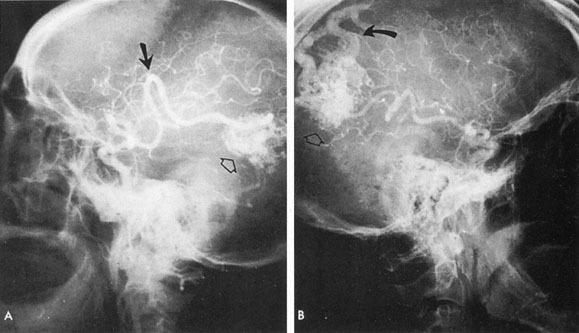

Fig. 7. Supratentorial arteriovenous malformation in a 28-year-old woman with a history of focal motor seizures for many years and a recent subarachnoid hemorrhage. A: Lateral projection carotid arteriogram demonstrating a huge deep hemispheral arteriovenous malformation. B: Frontal projection. C: Fundus photograph showing anomalous tortuous vasculature in each eye. No retinal arteriovenous shunt was detectable.

Fig. 8. Multiple supratentorial arteriovenous malformations (AVMs). A: Lateral projection of left carotid arteriogram shows dilated afferent artery (solid arrow) feeding the right hemispheric parietal AVM (open arrow). B: Right carotid injection fills a second, more posteriorly located, parietooccipital AVM (open arrow), which drains immediately to markedly dilated cortical veins (curved arrow).

Of particular interest are those AVMs that involve the occipital lobe (Fig. 9). The clinical differentiation of migraine from a cerebral AVM was previously regarded as difficult because the clinical features of occipital lobe AVMs include visual phenomena or headaches. However, in most cases the clinical distinction is possible. In 26 cases with occipital AVM, two distinct syndromes were defined in 18 patients: occipital epilepsy and occipital apoplexy.73 Focal seizures with occipital malformations consist of elementary visual sensations similar to the phenomena evoked by direct cortical stimulations. When seizure activity occurs in the striate cortex (area 17), the patient usually reports sensations of moving lights in the right or left homonymous fields. The sensations are poorly formed, episodic, usually brief, sometimes colored, and unassociated with the angular, scintillating figures so characteristic of migrainous cortical phenomena. Epileptic discharges from areas 18 and 19 cause photopsias that are unlikely to remain stationary and to flicker rapidly. The epileptic photopsias usually last only seconds; occasionally they last for a few minutes before the onset of a generalized seizure. In other instances only the brief visual episodes occur without spreading to produce a generalized seizure. Momentary dimming or blindness in one or both homonymous fields may be experienced with seizure activity in the occipital areas.

Fig. 9. Carotid arteriogram of an occipital lobe arteriovenous malformation (AVM). Lateral (A) and frontal (B) projections demonstrating a small occipital AVM (arrow). The patient was a 23-year-old woman who presented with severe apoplectic unilateral headache, total left homonymous hemianopia, and mild nuchal rigidity. Despite xanthochromic cerebrospinal fluid, she was initially diagnosed elsewhere as having migraine. An AVM was successfully resected, and a small occipital lobe hematoma was removed.